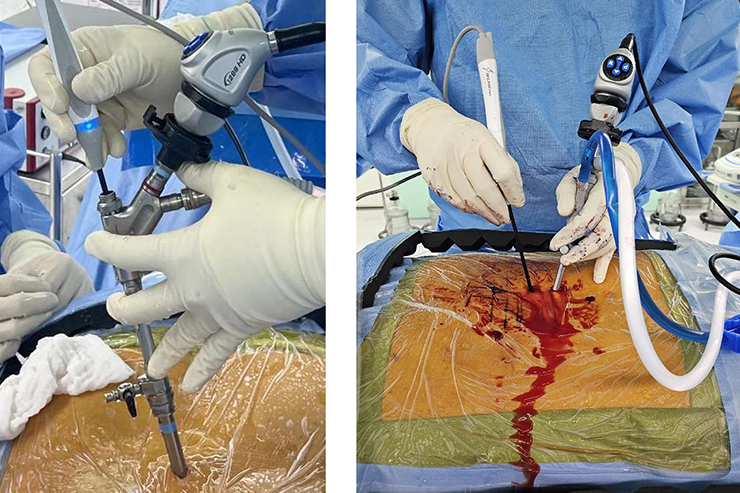

Endoscopic 4th Gen Spine Surgery (UBE) offers minimally invasive treatment for spine disorders with faster recovery, less pain, and precision....